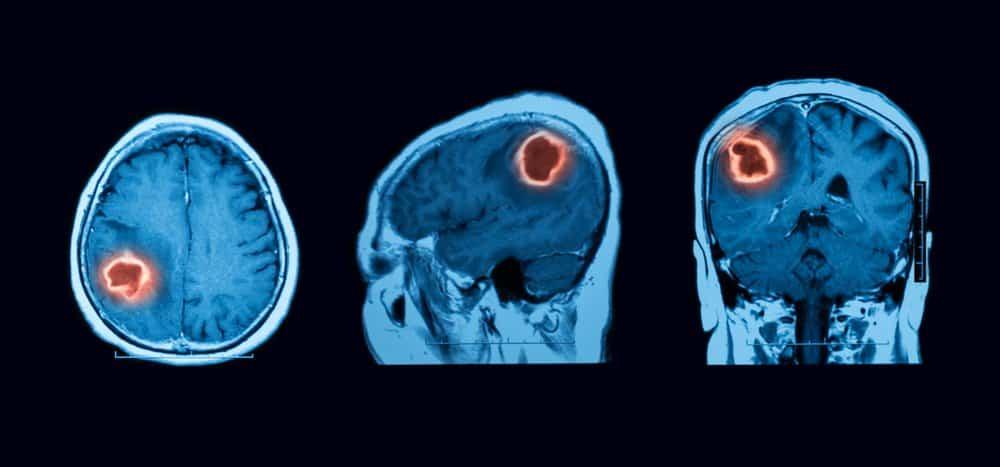

Nếu nghi ngờ bạn bị chảy máu dưới nhện, bác sĩ có thể yêu cầu chụp CT phần đầu (không có thuốc cản quang) ngay lập tức để phát hiện xuất huyết. Nếu chụp CT không cho thấy xuất huyết dưới nhện, bác sĩ có thể tiến hành chọc dò tủy sống. Bệnh nhân bị xuất huyết khoang dưới nhện thường có máu trong dịch não tủy. Một số xét nghiệm khác bao gồm:

- Chụp cộng hưởng từ (MRI) và cộng hưởng từ mạch máu (MRA) (đôi khi).